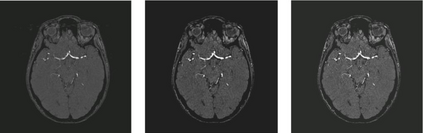

Time-of-Flight Magnetic Resonance Angiographs (TOF-MRAs) enable visualization and analysis of cerebral arteries. This analysis may indicate normal variation of the configuration of the cerebrovascular system or vessel abnormalities, such as aneurysms. A model would be useful to represent normal cerebrovascular structure and variabilities in a healthy population and to differentiate from abnormalities. Current anomaly detection using autoencoding convolutional neural networks usually use a voxelwise mean-error for optimization. We propose optimizing a variational-autoencoder (VAE) with structural similarity loss (SSIM) for TOF-MRA reconstruction. A patch-trained 2D fully-convolutional VAE was optimized for TOF-MRA reconstruction by comparing vessel segmentations of original and reconstructed MRAs. The method was trained and tested on two datasets: the IXI dataset, and a subset from the ADAM challenge. Both trained networks were tested on a dataset including subjects with aneurysms. We compared VAE optimization with L2-loss and SSIM-loss. Performance was evaluated between original and reconstructed MRAs using mean square error, mean-SSIM, peak-signal-to-noise-ratio and dice similarity index (DSI) of segmented vessels. The L2-optimized VAE outperforms SSIM, with improved reconstruction metrics and DSIs for both datasets. Optimization using SSIM performed best for visual image quality, but with discrepancy in quantitative reconstruction and vascular segmentation. The larger, more diverse IXI dataset had overall better performance. Reconstruction metrics, including SSIM, were lower for MRAs including aneurysms. A SSIM-optimized VAE improved the visual perceptive image quality of TOF-MRA reconstructions. A L2-optimized VAE performed best for TOF-MRA reconstruction, where the vascular segmentation is important. SSIM is a potential metric for anomaly detection of MRAs.